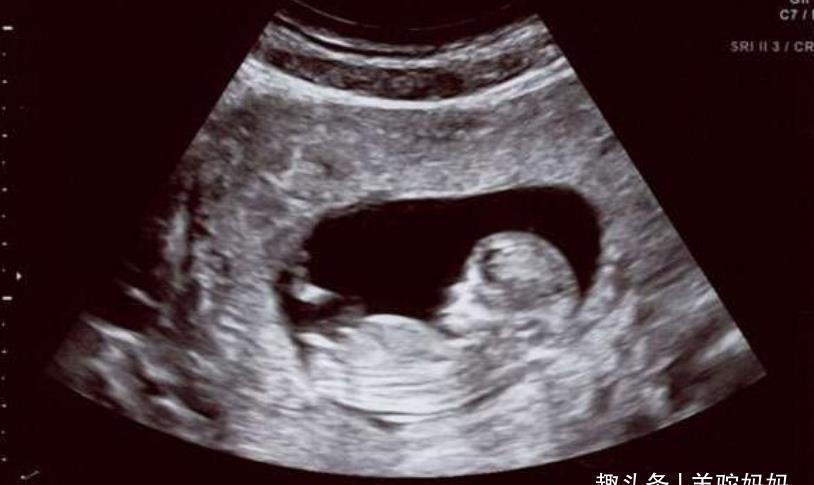

比如看着日益变大的肚子,这种成就感真的是溢于言表,并且在每一次产检的时候都能和宝宝见到短暂的一面。

孕妈真的只有在产检之后才是真正将悬着的心放下来了,因为不产检期间是真的无法感知宝宝到底发育的好不好,产检之后给出结果宝妈才是真的能放心一点。